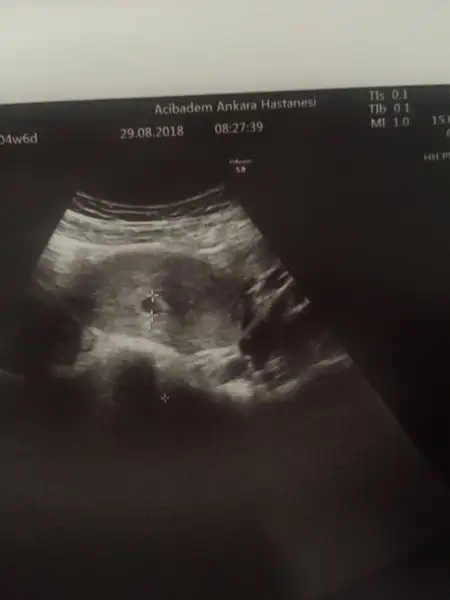

siz anlıyorsanız ultrason fotorafını göndersem yardımcı olur musunuz? kesenin içi dolu dedi doktor ama yolk kesesinden hiç bahsetmedi.

resmi yükledim.yaklaşınca içinde bişey var gibi ama tabi anladığım bi konu değil nedir ne değildir çözemedim.

Evet oluşum var gayette güzel bi yere yerleşmiş. Yolk sac var anembriyonik değil kesenin şekli gayet düzgün hatları sınırları muntazam . Rahat ol rahat zaten üç beş haftaya bulantı kusma kabusun olcak şuan tadını çıkar ve doya doya yemek ye su iç. Yemeğin suyuna ekmek ban ye.

Rica ederim ebeyim ve hep kadın doğum hastanesinde çalıştım . Kadın doğum acillerde de ultrason baka baka konuşa tartışa bişeyler birikti. Kafanı boşalt tadını çıkar evham kötü şartları iyiye çevirmez ama halihazırda iyi olanı bozabilir.pozitif oluyoruz. Gönlünce olsun herşey...